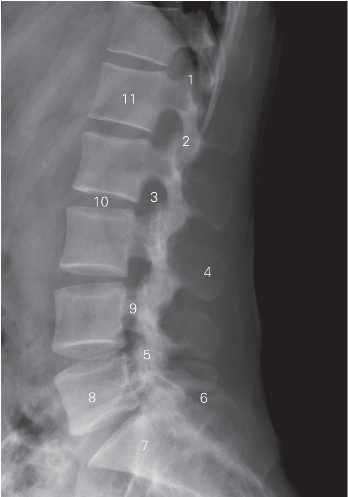

图6-5 腰椎侧位DR 平片

1 上关节突 superior articular process 2 下关节突 inferior articular process

3 椎间孔 foramen intervertebrale 4 棘突 spinous process

5 关节突关节 zygapophyseal joint 6 髂骨 ilium

7 骶骨 sacrum 8 第5腰椎 5th lumbar vertebra

9 椎弓峡部 isthmus vertebral arch

10 L2/3椎间隙 L2/3 lumber intervertebrale space

11 第1腰椎椎体 1st lumbar vertebral body